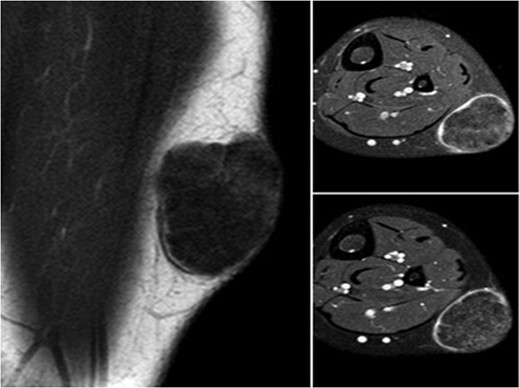

A 10-year-old boy presented with a 3-month history of pain and swelling in the left leg. Physical examination showed a 3 × 4 cm2 solid and mobile mass along the posterior aspect of the left leg. There were no history of trauma, weight loss or previous inflammatory disease. Radiographs showed calcification on the posterolateral side of the left cruris (Fig. 1). MRI indicated a solid soft tissue mass in the posterolateral side of the left cruris, which was observed to be hypointense in the T1A series, and hyperintense in the T2A series. The mass had regular margins, and exhibited peripheral contrast enhancement with a 41 × 30 × 27 mm3 size (Fig. 2). Lipoma, epidermoid cyst, sebaceous cyst, calcified hematoma and giant-cell tumor were considered in differential diagnosis. Incisional biopsy was performed. Histopathological examination confirmed as pilomatrixoma (Fig. 3). Thus, a complete resection of the mass was performed. There has been no recurrence, either clinically or radiologically, in subsequent 1-year period.

Magnetic resonance image of the homogeneous lesion, visualized with regular margins and including patch-like areas.